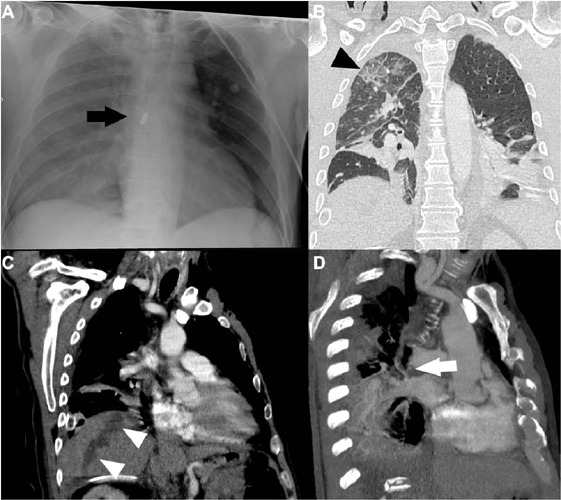

Abstract Image